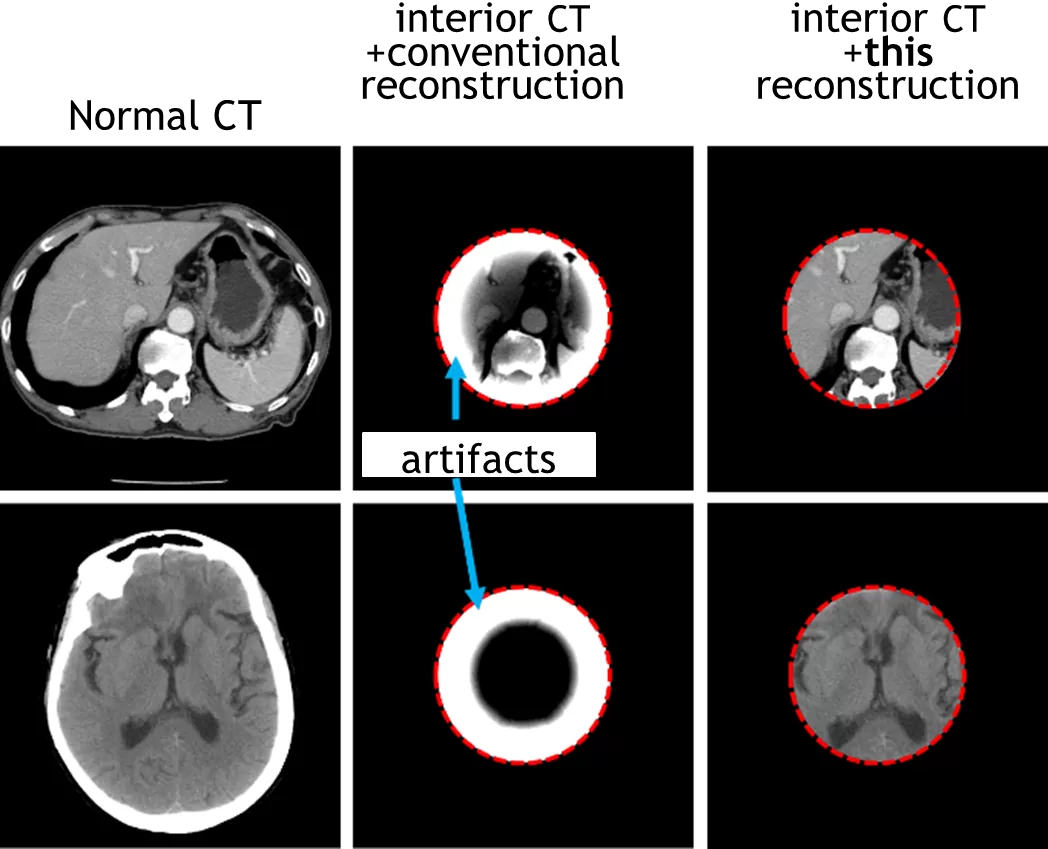

ヒトの胴体と脳に対しインテリアCT測定を行ったのち、従来方法と本技術の方法でCT画像を再構成した。その結果、従来方法ではアーティファクト(誤差)のためほとんどの情報が欠落したが(下図中央)、本技術の方法では、通常のCT画像と遜色ない高精度のインテリアCT画像が取得できた(下図右側)。この際のX線被曝量は通常のCTに比べて1/4~1/8に相当する。